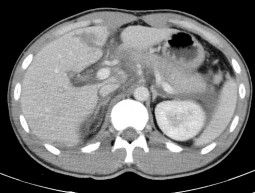

Hình 4.3: CTG độ III, tổn thương rách nhu mô hạ phân thùy IV dạng các đường giảm tỷ trọng, kém ngấm thuốc sau tiêm, dài nhất 45mm.

Nguồn: BN Vũ Văn Kh, 58t HS: 2115068